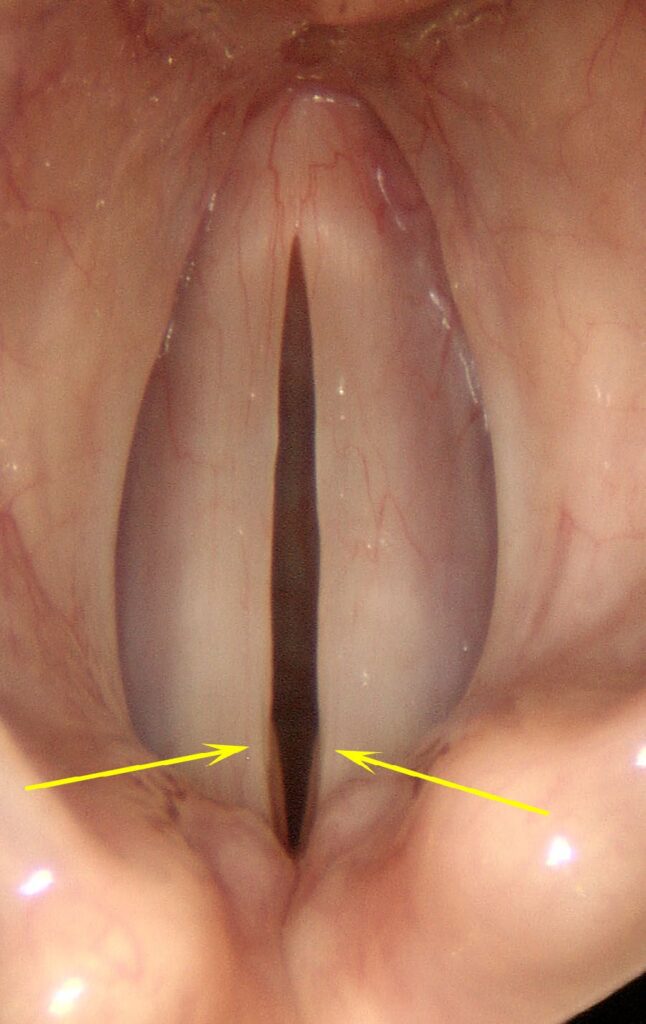

Central Gap

If the vocal cord muscles are not exercised regularly, they atrophy and can no longer tense to a straight line. They remain concave even when the vocal processes are completely closed, creating a central gap. Aging contributes as well — the vocal cords sag with aging as they lose elasticity, producing a nearly oval-shaped gap with pointed ends. An asymmetric central gap is created when tension within one vocal cord is reduced, allowing it to oscillate further laterally than the other side, suggesting a thyroarytenoid muscle paresis.